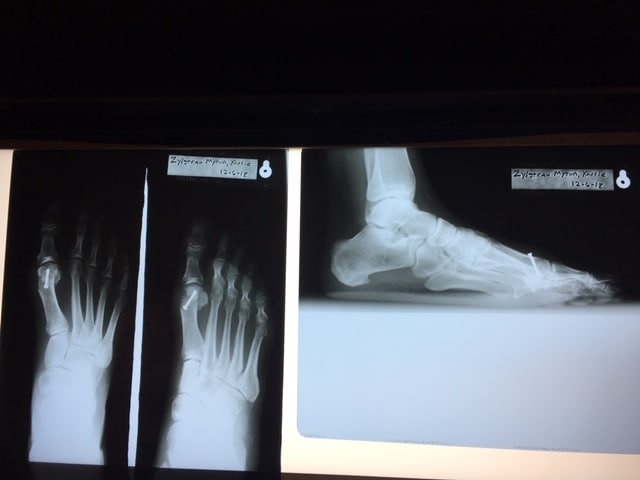

The first photo shows my sad and crooked foot BEFORE. Below is my corrected foot with a screw through the top that may or may not set off the security alarms when I get to those metal detectors. We will see.